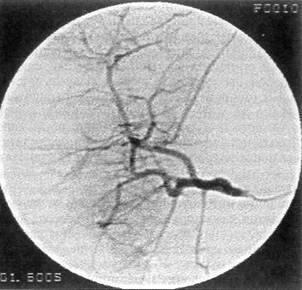

Рис. 16. Контрольная ангиогепатография больного Ч., 30 лет, после рентгеноэндоваскулярной эмболизации поврежденной ветви печеночной артерии спиралями Гиан-турко. Гематома контрастом не заполняется

пичная резекция правой доли печени, наложена холецистостома, ушита рана почки, диафрагмы, грудной стенки, дренирована плевральная и брюшная полости. Хирург использовал комбинированный доступ — срединный разрез дополнил подреберным, справа 21.05 санавиацией больной доставлен в клинику. Состояние тяжелое, бледен, склеры субиктеричны, живот умеренно вздут, болезненный, печень выступает из-под реберной дуги на два поперечника пальца. Стул 2 раза в сутки; кал неоформленный, черного цвета. Гипертермия. На обзорной рентгенограмме живота отмечено высокое стояние правого купола диафрагмы. Наличие поддиафрагмального абсцесса подтверждено компьютерным исследованием Оперирован Сняты швы с послеоперационной раны в правом подреберье Из подпеченочного и поддиафрагмального пространства выделяются гной, старая кровь в смеси с детритом печени. Установлено, что резецированный край V сегмента прошит П-образными швами, а в области VII—VIII сегментов имеется рана размером 8,0x6,0 см, с рваными краями, заполненная гноем и сгустками крови. При ревизии раны возникло артериальное кровотечение Рана тампонирована «сигарообразными» тампонами. При ушивании раны брюшной стенки возникло кровотечение по дренажам. При ревизии — интенсивное кровотечение из раны печени. Рана повторно тампонирована четырьмя салфетками, которые стали пропитываться кровью; больной транспортирован в отделение рентгенохирургии. Трансфеморальным доступом справа выполнена аорто-, целиако- и селективная ангиогепатография. На ангиограммах: патологии в бассейне верхней брыжеечной и почечной артерий не выявлено; в артерии передневерхнего сегмента правой печеночной артерии обнаружена экстравазация раствора контраста в полость диаметром 2 см с длительной задержкой в ней контраста (рис 15). В поврежденный сосуд подведен катетер, через который введены спирали Гиантурко: дистальнее и проксимальнее гематомы. Контрольная гепатография гематома не заполняется (рис. 16). Послеоперационное течение благоприятное. Больной выписан из клиники 22.06 в удовлетворительном состоянии.